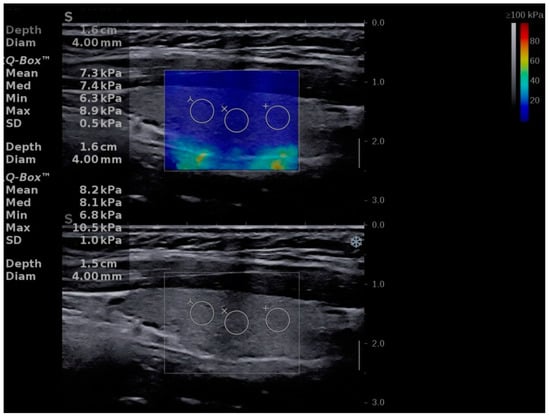

| Mean TS values | 15.51 ± 4.76 | 10.41 ± 2.01 | p < 0.0001 |

| Left lobe mean values | 15.46 ± 4.77 | 10.32 ± 2.22 | p < 0.0001 |

| Right lobe mean values | 15.56 ± 5.22 | 10.50 ± 2.14 | p < 0.0001 |